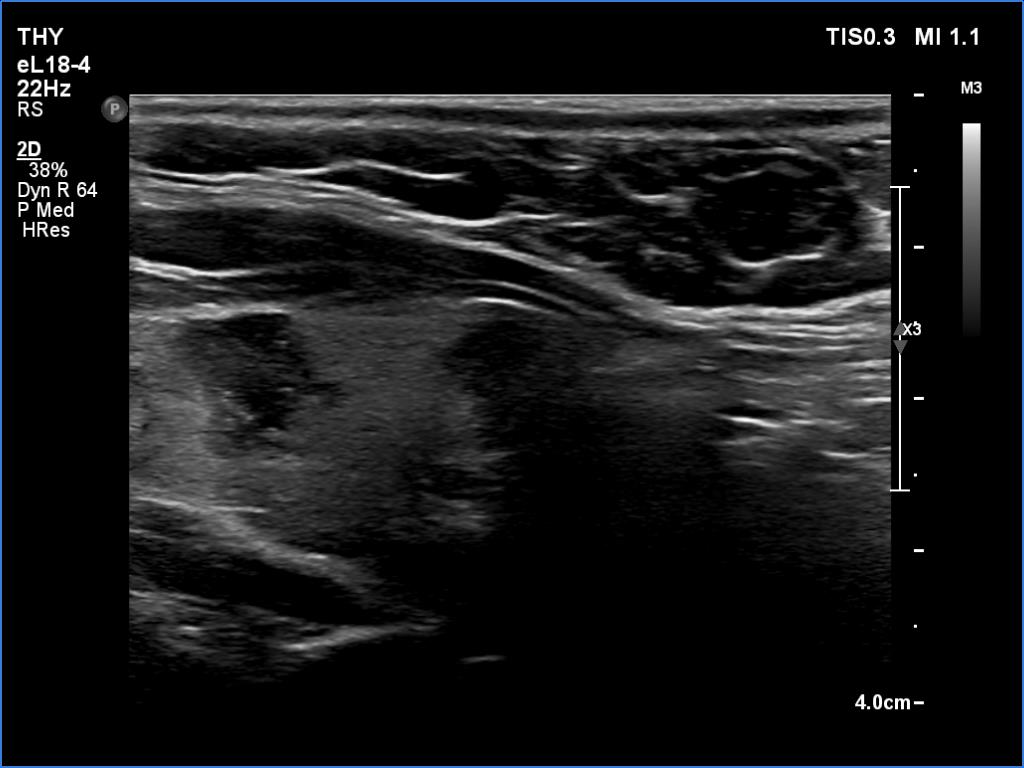

First examination (first and second rows of images):

Clinical data: A 37-year-old woman requested a screening. Recently, her mother was diagnosed with hypothyroidism and we suggested to screen the first-degree female relatives for autoimmune thyroid disease.

Palpation: no abnormality.

Laboratory tests: TSH 8.79 mIU/L, aTPO 808 U/mL.

Ultrasonography. The thyroid was echonormal or minimally hypoechoic and had several discrete, more hypoechoic areas. Two of them in the left lobe were remarkable because of irregular borders and nonparallel orientation.

Cytology was performed from the larger lesion in the left lobe and resulted in Hashimoto's thyroiditis.

Daily 50 microgram levothyroxine was administered. We suggested repeat ultrasound and cytology in a year.